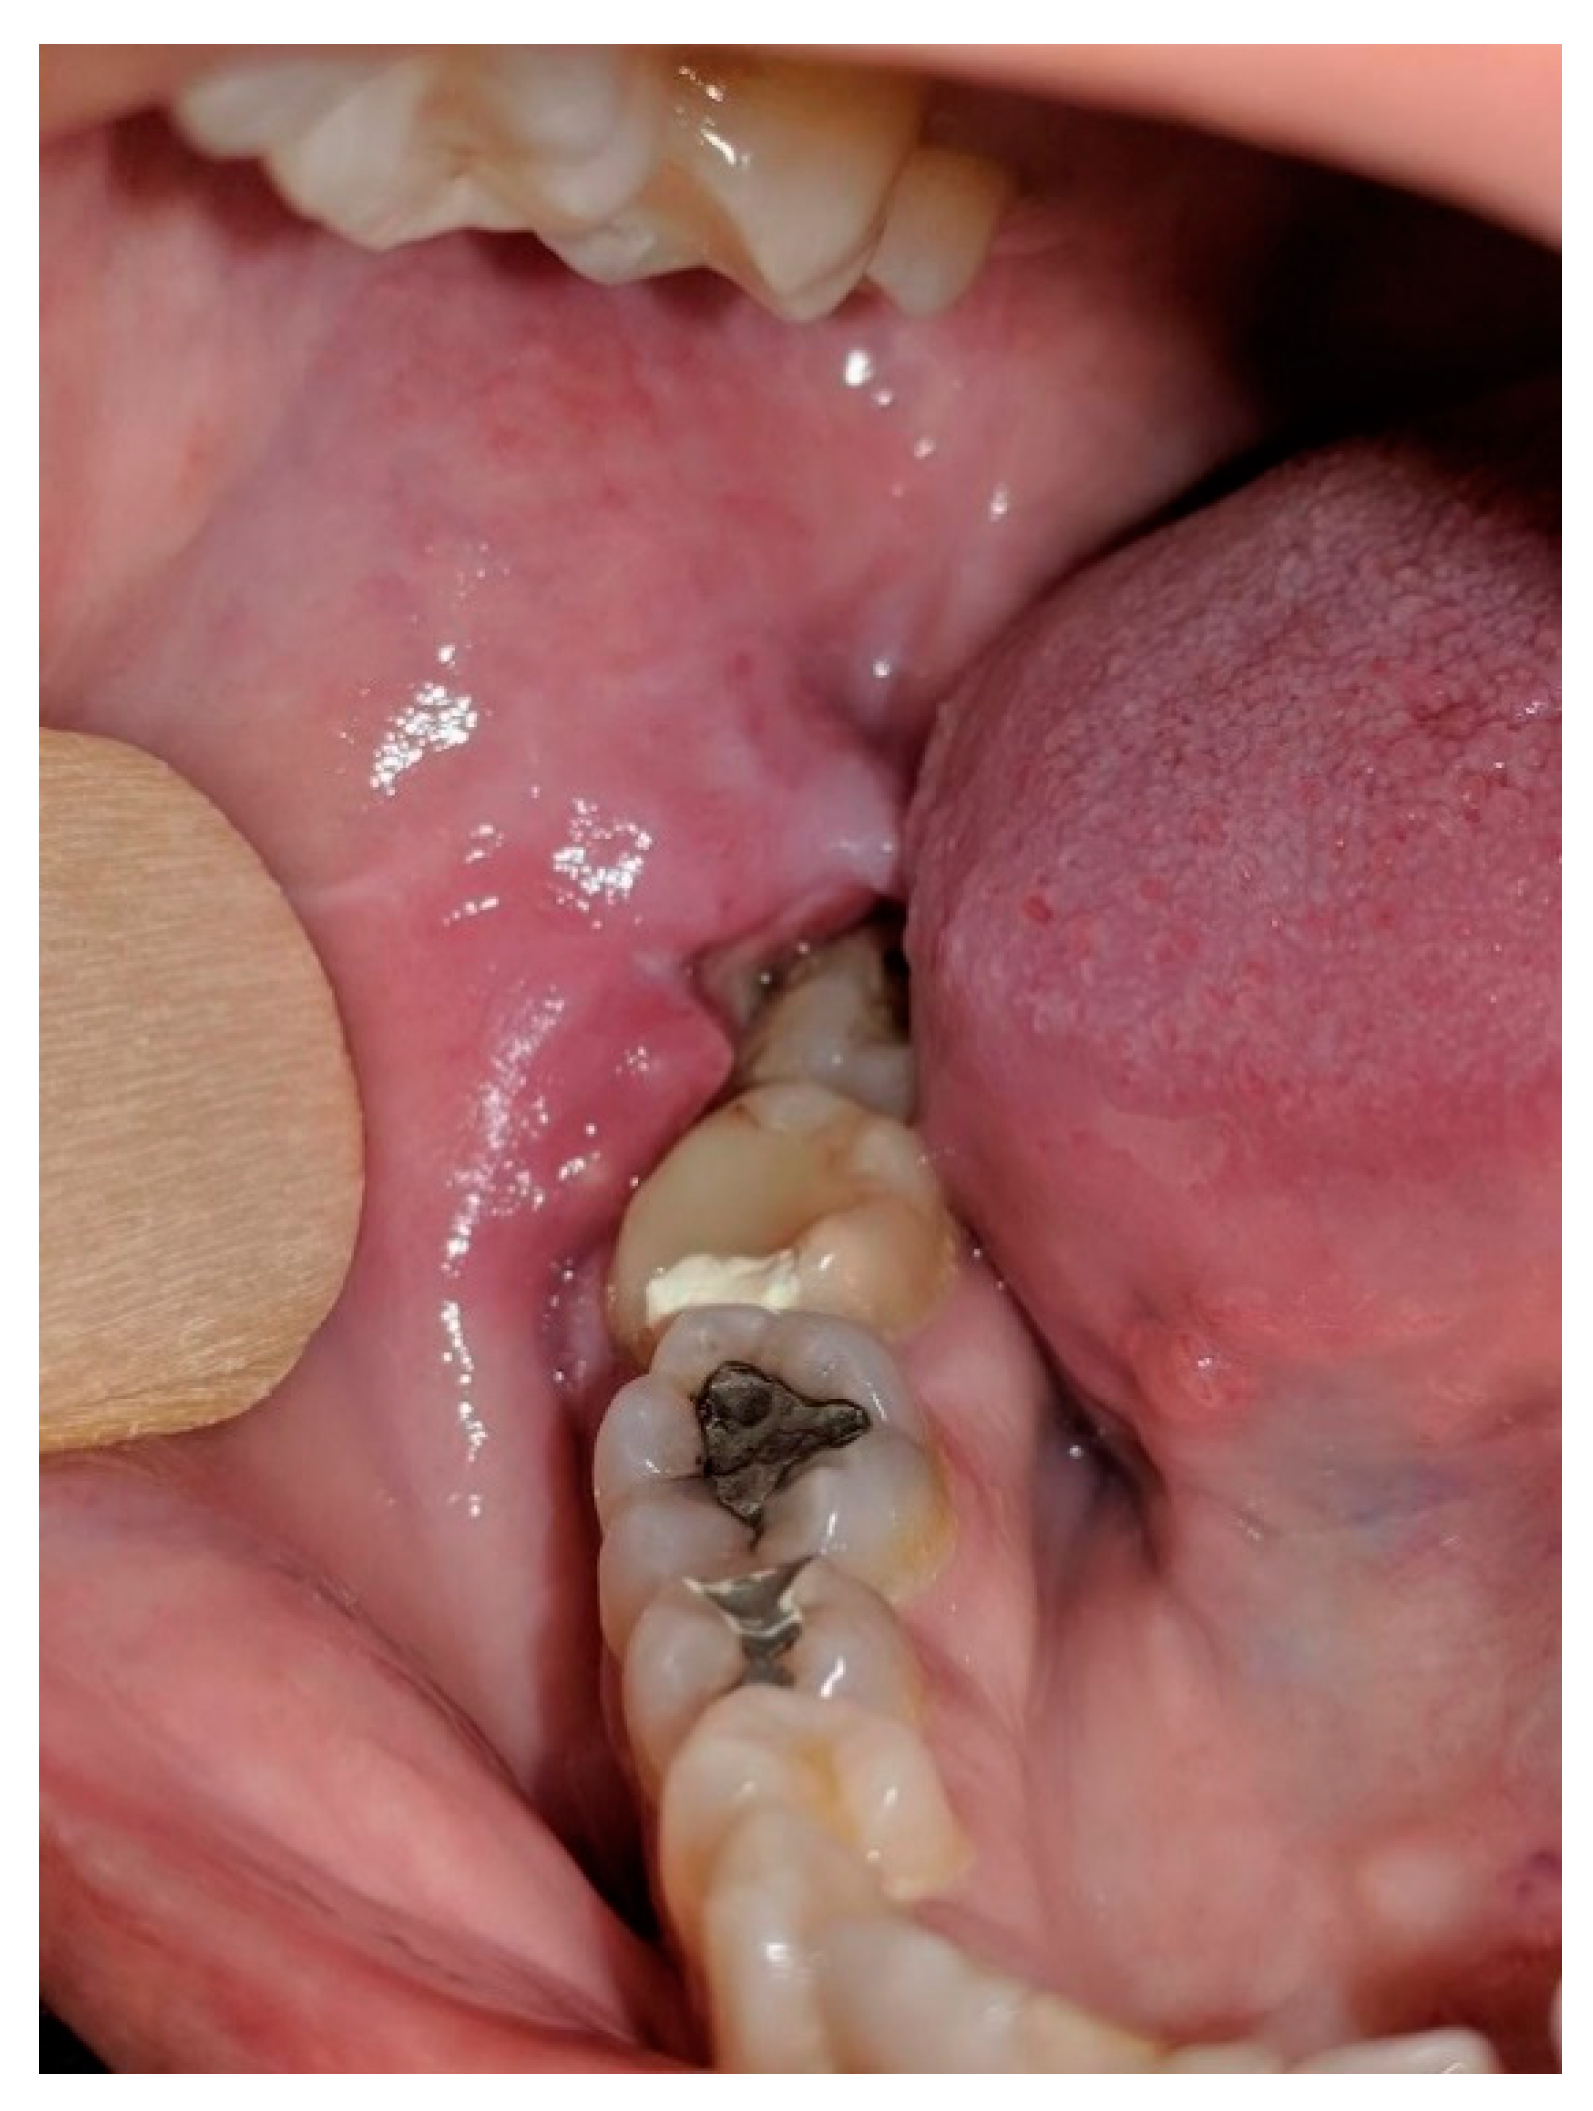

Pancreatic Carcinoma Metastatic to the Gingiva

2. Case Report